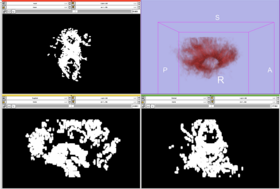

As a main purpose, the stochastic tractography module helps to evaluate connectivity between two regions of the Grey Matter of the brain using ROIs (Region Of Interest) as inputs. These ROIs define grey matter regions ensuring a specific neurophysiological function. Extensively, study involving more than two regions could still be done by pairing the regions two by two and computing them separetely to finally gather the results.

The stochastic tractography module interface offers to users a real workflow allowing to

smooth with a Half Width Full Maximum filter,

generate a brain mask,

create a DTI (Diffusion Tensor Image) tensor with standard measures like fractional anisotropy (FA), mode and trace,

run tractography and deal with connection maps.